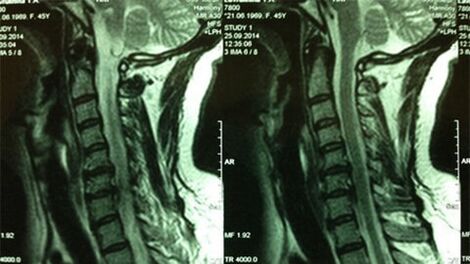

- X -Rings of the Cervical Department;In the initial phase of the process, the magnetic resonance imaging of the cervical department will be more instructive - will guarantee a high quality display of solid and soft tissues - will show the condition of the intervertebral discs, the presence of osteophytes, the deformations, the damage to the nerve roots and the blood vessels;will evaluate the condition of ligaments, muscles, bone tissue;